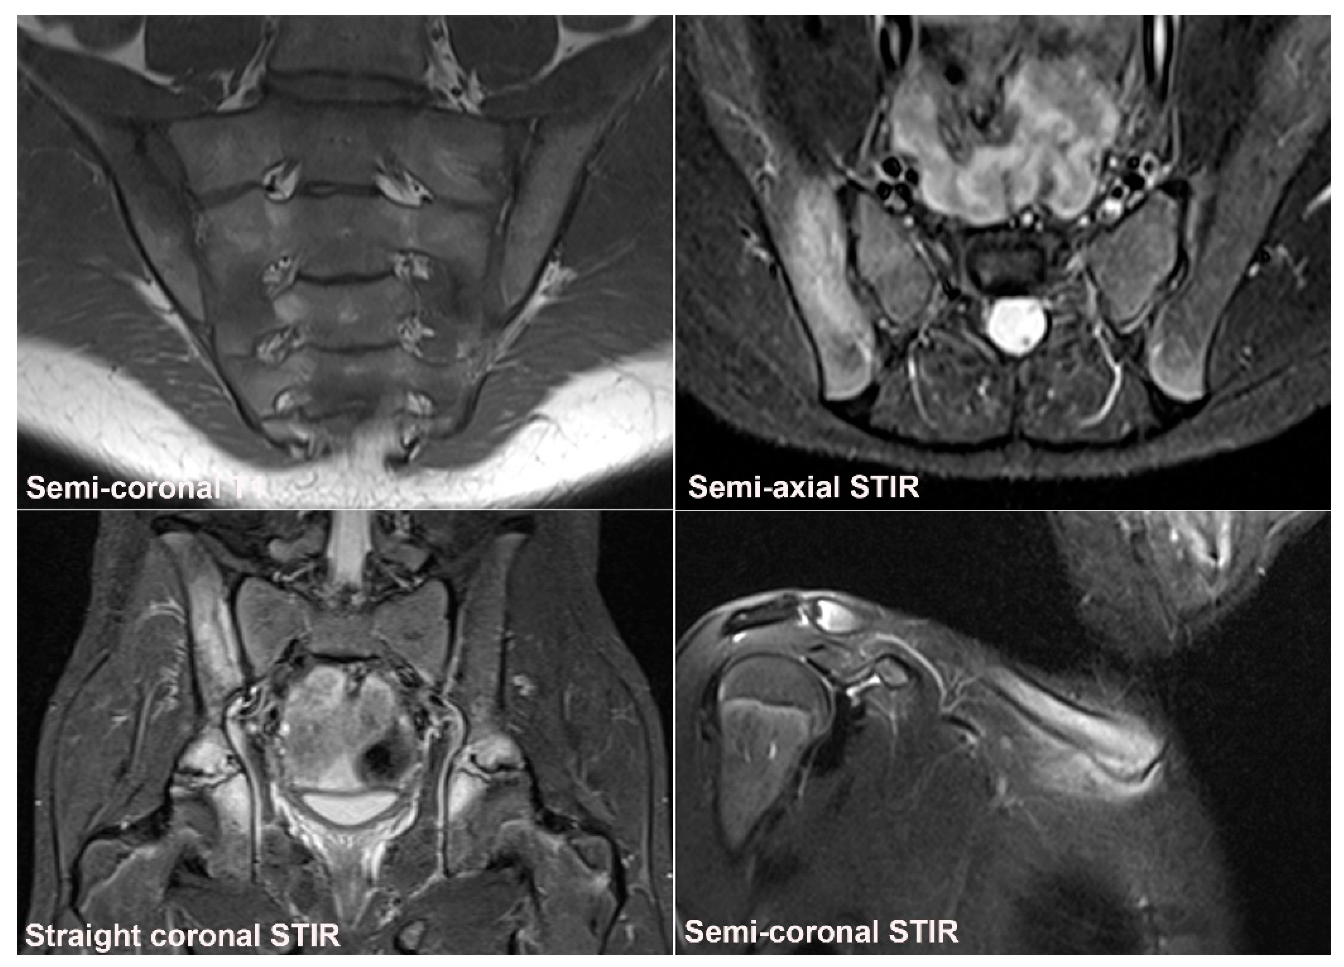

2. SIJ Appearance in Childhood

3. Normal SIJ Anatomy in Adults and Technical MRI Aspects

- Weber, U.; Jurik, A.G.; Zejden, A.; Larsen, E.; Jørgensen, S.H.; Rufibach, K.; Schioldan, C.; Schmidt-Olsen, S. MRI of the Sacroiliac Joints in Athletes: Recognition of Non-Specific Bone Marrow Oedema by Semi-Axial Added to Standard Semi-Coronal Scans. Rheumatology 2020, 59, 1381–1390. [Google Scholar] [CrossRef]